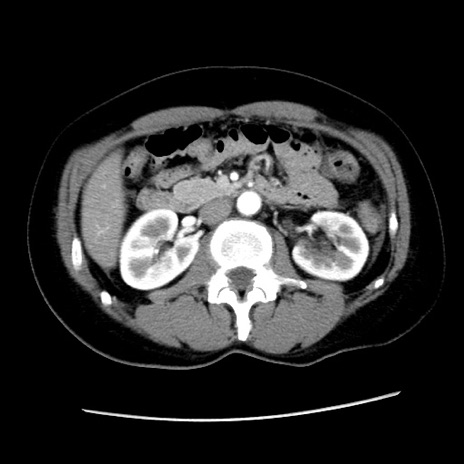

矢状断像

【症例】 50歳代女性

【主訴】 腹痛

【現病歴】前日生レバーを食べた。今朝に排便あり。 昼前に突然発症の腹痛を生じ、当院救急外来を受診した。

【既往歴】 子宮筋腫にてで子宮全摘後

【身体所見】 意識清明、腹部:平坦、軟、下腹部やや左を中心に圧痛・反跳痛あり、筋性防御あり

【データ】WBC 7800、CRP 0.07